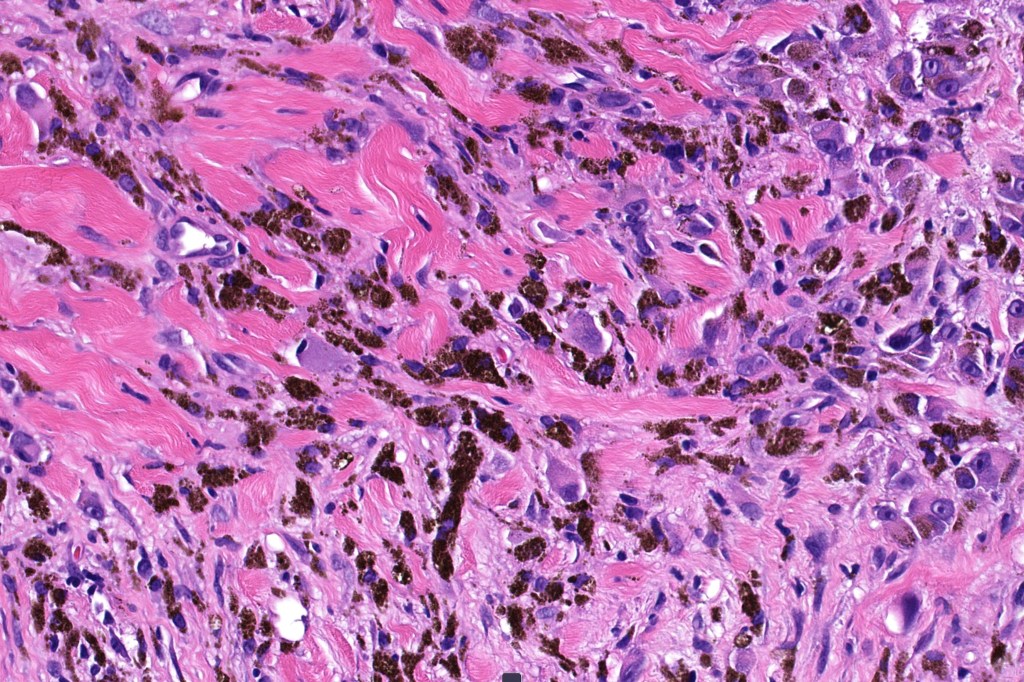

- Melanoma arising in a pre-existent blue nevus (common or more often cellular) or denritic melanocytosis including nevus of Ota, Ita & pilar neurocristic hamtoma

- Melanoma in which blue nevus-like features (dendritic cells & melanophages) are seen within a spindled or epithelioid melanoma

Histological features

•Develops within a precursor lesion as one or more nodules of epithelioid or spindled cell melanoma

•Or melanoma showing admixed blue nevus-like features (dendritic cells and melanophages) in the absence of a precursor lesion